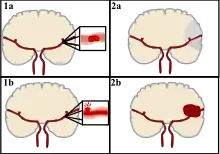

Stroke can be classified into two major categories: ischemic and hemorrhagic.[19] Ischemic stroke is caused by interruption of the blood supply to the brain, while hemorrhagic stroke results from the rupture of a blood vessel or an abnormal vascular structure. About 87% of stroke is ischemic, with the rest being hemorrhagic. Bleeding can develop inside areas of ischemia, a condition known as "hemorrhagic transformation." It is unknown how many cases of hemorrhagic stroke actually start as ischemic stroke.[2]

Ischemic

During ischemic stroke, blood supply to part of the brain is decreased, leading to dysfunction of the brain tissue in that area. There are four reasons why this might happen:

Hemorrhagic

There are two main types of hemorrhagic stroke:[29][30]

- Intracerebral hemorrhage, which is bleeding within the brain itself (when an artery in the brain bursts, flooding the surrounding tissue with blood), due to either intraparenchymal hemorrhage (bleeding within the brain tissue) or intraventricular hemorrhage (bleeding within the brain's ventricular system).

- Subarachnoid hemorrhage, which is bleeding that occurs outside of the brain tissue but still within the skull, and precisely between the arachnoid mater and pia mater (the delicate innermost layer of the three layers of the meninges that surround the brain).